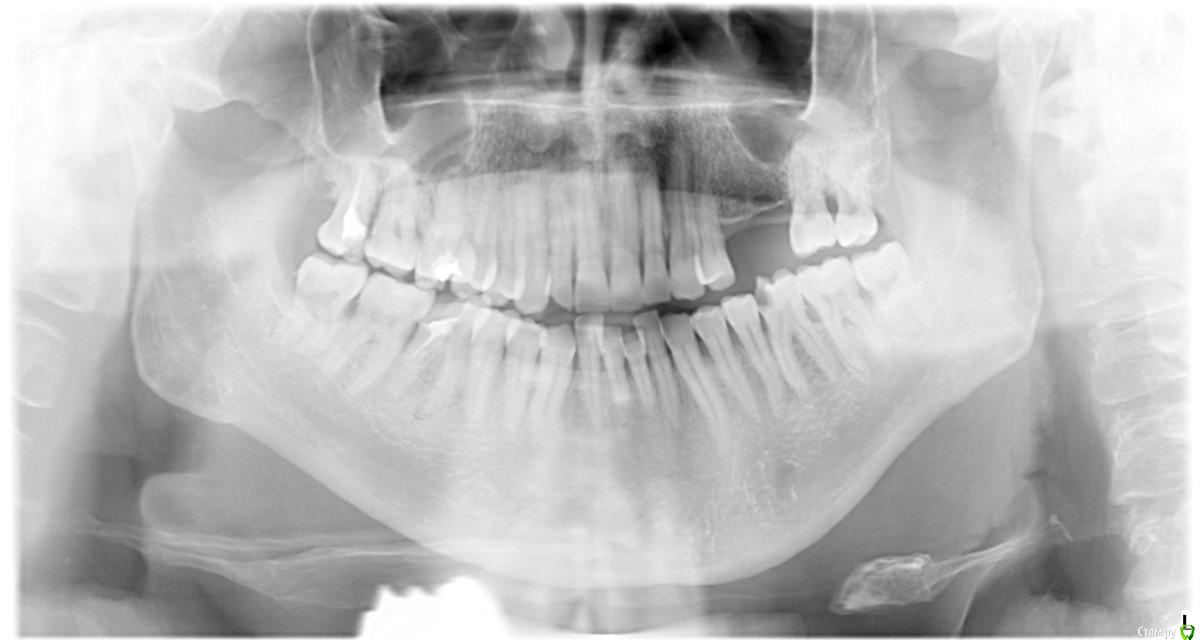

Соколов Виктор Опубликовано 18 января, 2015 Поделиться Опубликовано 18 января, 2015 Добрый день! Мне 58 лет. Решил заняться лечением зубов. Хочу поставить импланты на 5 и 6 зубы наверху слева. Возможно ли это, учитывая возраст и нужен ли синус-лифтинг? И что делать с верхним 6 зубом справа? Попытаться перелечить или только удаление? Профгигиену сделал. Прошу проконсультировать по объёму работ. Заранее благодарен. Ссылка на комментарий

SDC Опубликовано 18 января, 2015 Поделиться Опубликовано 18 января, 2015 http://s017.radikal.ru/i427/1501/0a/678eebf2ac62.png Синие стрелки - зубной камень и локализованный пародонтит.Фиолетовая - кариесКрасные - периодонтит. Скорее всего перелечивание с последующим протезированием возможны.Салатовые - имплантатыУстановка имплантата в обл. 25 зуба возможна без синус-лифтинга, в обл. 26 есть варианты, которые можно рассмотреть после исследования КТ: короткий имплантат без синус-лифтинга, имплантат 8-10 мм, с закрытым синус-лифтингом и открытый синус-лифтинг с установкой имплантата любой длины.27 зуб сместился вперед, поэтому на имплантатах 2 коронки с размерами премоляров. 1 Ссылка на комментарий